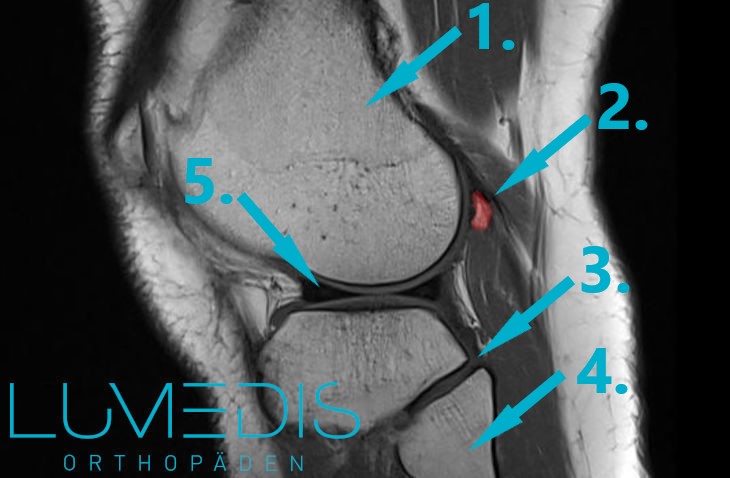

MRT Fabella in der Kniekehle

MRT Knie seitlich (T2):

Ein Muskelfaserriss der Kniekehle kann auftreten, wenn Muskelfasern der hinteren Oberschenkelmuskulatur reißen oder verletzt werden. Dies kann durch plötzliche oder ungewohnte Bewegungen, Überbelastung der Muskulatur oder direkte Traumata verursacht werden. Betroffene leiden bei einem Muskelfaserriss der Kniekehle meist unter starkenSchmerzen im Bereich des hinteren Oberschenkels und der Kniekehle, die zu einer eingeschränkten Beweglichkeit im Kniegelenk führen können. Typischerweise nimmt die Schmerzintensität bei körperlicher Aktivität zu. In manchen Fällen kann ein Muskelfaserriss der hinteren Oberschenkelmuskulatur auch zu Schwellungen und Blutergüssen im Bereich der Kniekehle führen.